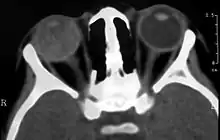

Imaging studies such as ultrasonography (US), Computerized Tomography (CT) and Magnetic Resonance Imaging (MRI) can aid diagnosis. On ultrasound, Coats' disease appears as a hyperechoic mass in the posterior vitreous without posterior acoustic shadowing; vitreous and subretinal hemorrhage may often be observed.[7][8]

On CT, the globe appears hyperdense compared to normal vitreous due to the proteinaceous exudate, which may obliterate the vitreous space in advanced disease. The anterior margin of the subretinal exudate enhances with contrast. Since the retina is fixed posteriorly at the optic disc, this enhancement has a V-shaped configuration.[2]